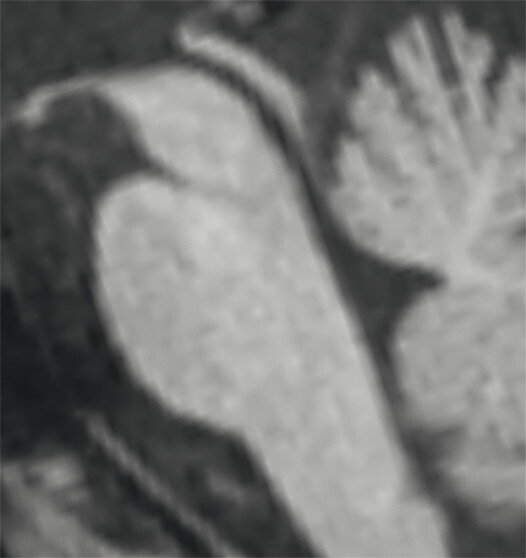

- Bei der Bestimmung der Midbrain/Pons-Ratio werden auf sagittalen Mittellinienaufnahmen Ellipsen in Pons (ohne Tegmentum pontis) und Mittelhirn gelegt und die kurzen Durchmesser der Ellipsen zueinander in Beziehung gesetzt. Bei Normalpersonen beträgt der kurze Mittelhirndurchmesser ca. ⅔ des kurzen Ponsdurchmessers, bei Patienten oder Patientinnen mit progressiver supranukleärer Blickparese ist er auf etwa 50% oder weniger erniedrigt, bei Personen mit Multisystematrophie vom zerebellären Typ auf über ⅔ erhöht [8].

c Planimetrische Messungen zur Bestimmung des MR-Parkinson-Index.